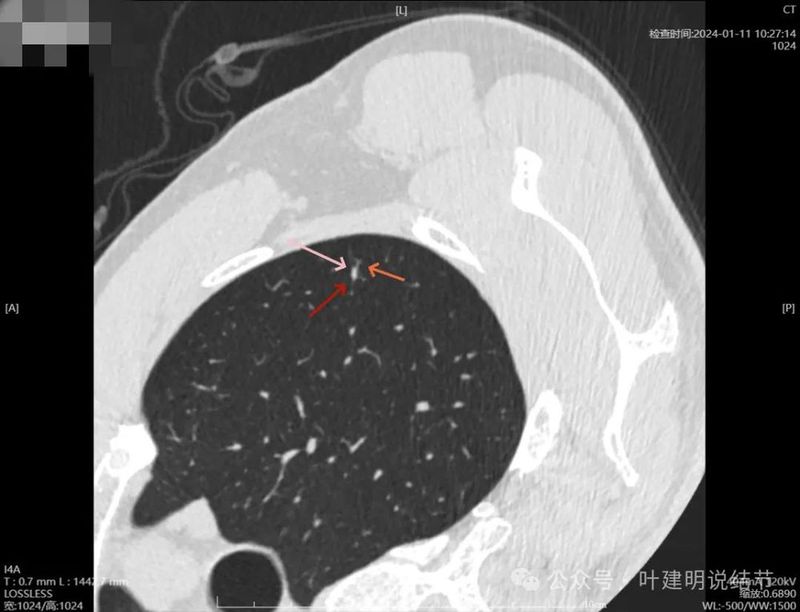

2024年1月靶重建:

病灶密度较高,有月牙铲征,轮廓显模糊。

有微小血管,密度较高,有偏实性成分,磨玻璃密度淡,边界稍糊。

似乎密度过高,毛刺不是太锐利。

密度太高,而且偏长条状。

边缘区密度高,条状。

实性部分密度过高,磨玻璃部分密度淡且瘤肺边界不太清。